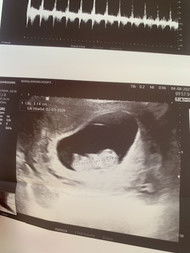

10วีค พอดีคร้า ตรวจวันนี้สดๆร้อนๆ☺️❤️

10W 6D ขนาด4.96cm หัวใจเต้น180ครั้งต่อนาทีค่ะ